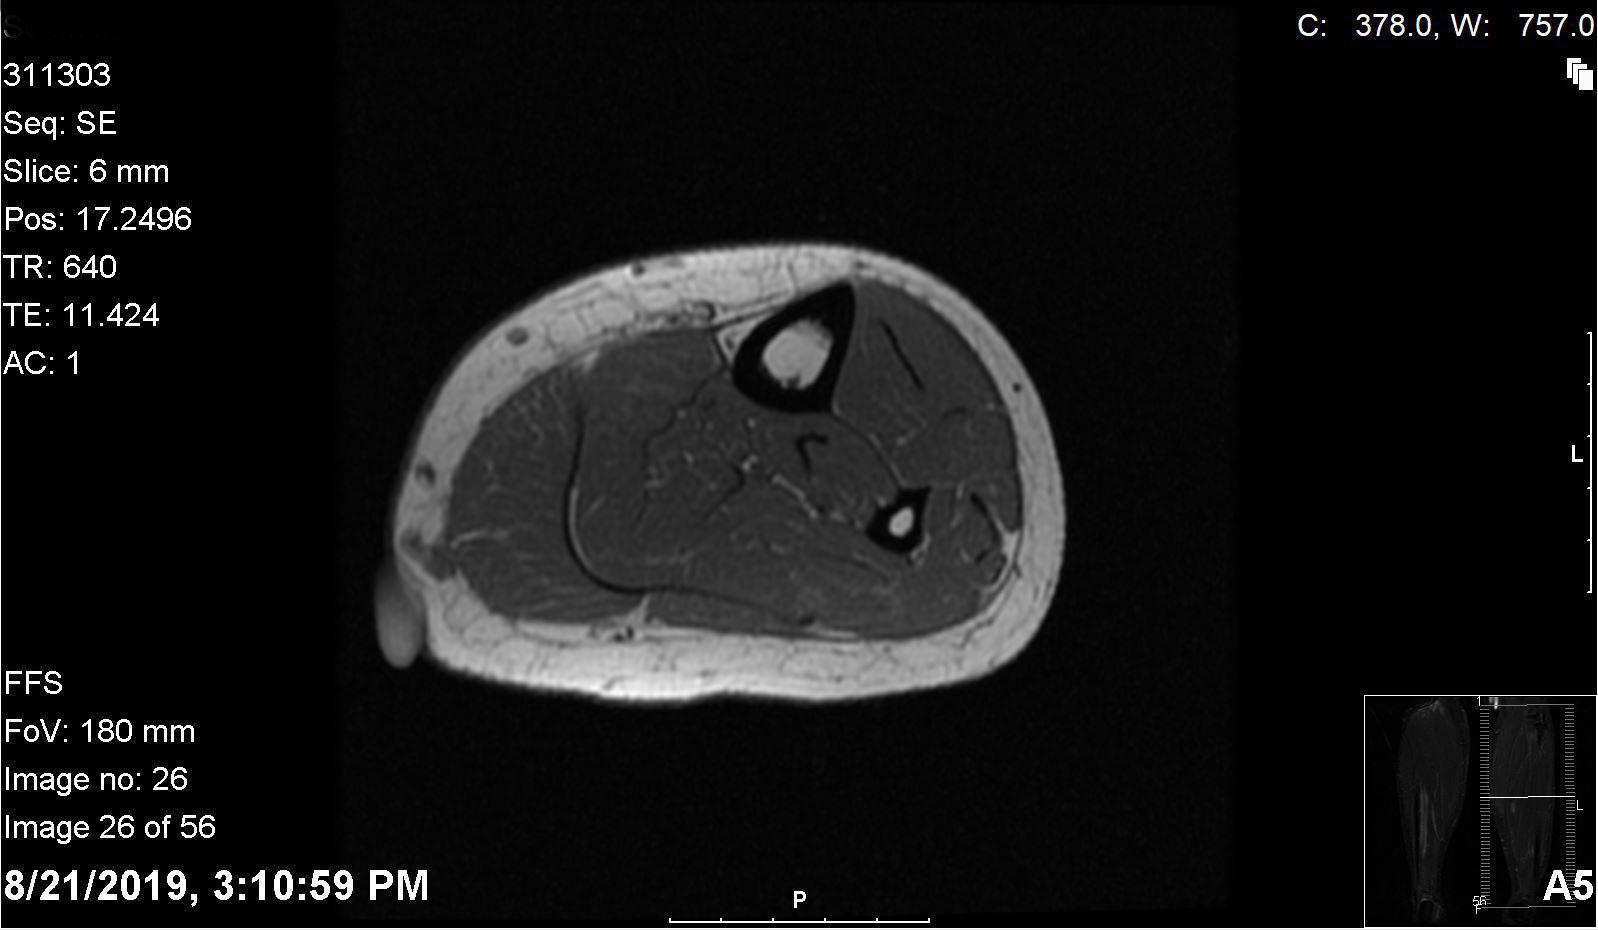

Tibialis anterior muscle hernia A rare cause of leg pain. Case report Calf Leg Hernia Muscle hernias are abnormal protrusions of muscle through a fascial weakness or acquired fascial defect, with the lower leg being the most commonly involved extremity. Conservative treatment did not lead to success. Ultrasound and mri imaging confirmed the diagnosis of muscle hernia of the medial gastrocnemius on the right leg. Most muscle hernias occur in the lower leg and affect. Calf Leg Hernia.

Figure 1 from Transfascial Muscular Hernias Semantic Scholar Calf Leg Hernia Ultrasound and mri imaging confirmed the diagnosis of muscle hernia of the medial gastrocnemius on the right leg. Muscle hernias are abnormal protrusions of muscle through a fascial weakness or acquired fascial defect, with the lower leg being the most commonly involved extremity. A sports hernia (also called athletic pubalgia, sportsman’s hernia and gilmore’s groin) is an injury (usually a. Calf Leg Hernia.

Transfascial muscular hernia An unusual cause for a “hide and seek Calf Leg Hernia Ultrasound and mri imaging confirmed the diagnosis of muscle hernia of the medial gastrocnemius on the right leg. Muscle hernias are abnormal protrusions of muscle through a fascial weakness or acquired fascial defect, with the lower leg being the most commonly involved extremity. A total of 132 patients were identified. Conservative management was carried out in 22 (16.7%) patients, and. Calf Leg Hernia.

Transfascial muscular hernia An unusual cause for a “hide and seek Calf Leg Hernia Other muscles and sites, including the upper extremities, can be involved. Conservative management was carried out in 22 (16.7%) patients, and 110 (83.3%). Conservative treatment did not lead to success. A total of 132 patients were identified. Ultrasound and mri imaging confirmed the diagnosis of muscle hernia of the medial gastrocnemius on the right leg. A sports hernia (also called. Calf Leg Hernia.